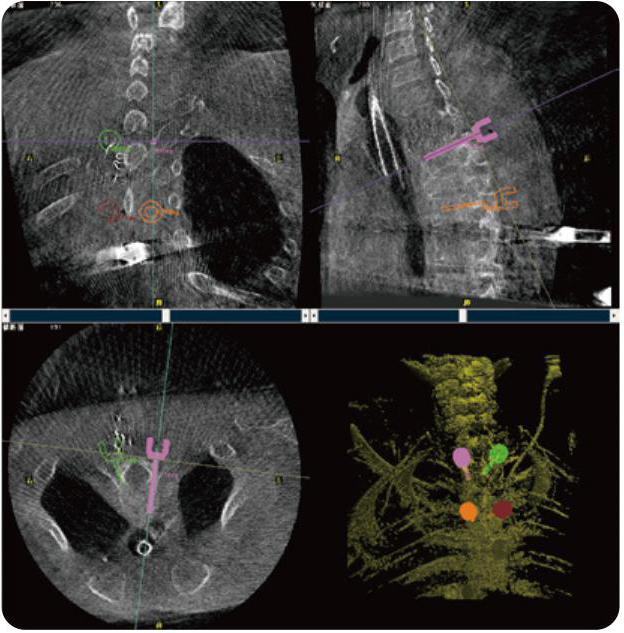

PL300B可應(yīng)用于多節(jié)段脊柱外科手術(shù),輔助醫(yī)生定位病灶部位,為脊柱外科手術(shù)(經(jīng)皮椎體成形術(shù)、椎弓根螺釘內(nèi)固定術(shù)等術(shù)式)提供術(shù)前手術(shù)流程規(guī)劃、入釘位置、角度可視化引導(dǎo),模擬仿真入釘輔助。

PL300B搭配普愛醫(yī)療自主研發(fā)生產(chǎn)的平板3D C形臂,借助一體化自適應(yīng)配準(zhǔn)( 軌跡配準(zhǔn))技術(shù),通過(guò)追蹤C(jī)形臂三維采集軌跡,自動(dòng)完成圖像坐標(biāo)建立和系統(tǒng)坐標(biāo)配準(zhǔn)。配準(zhǔn)精度更高,操作步驟少,系統(tǒng)運(yùn)作效率高。